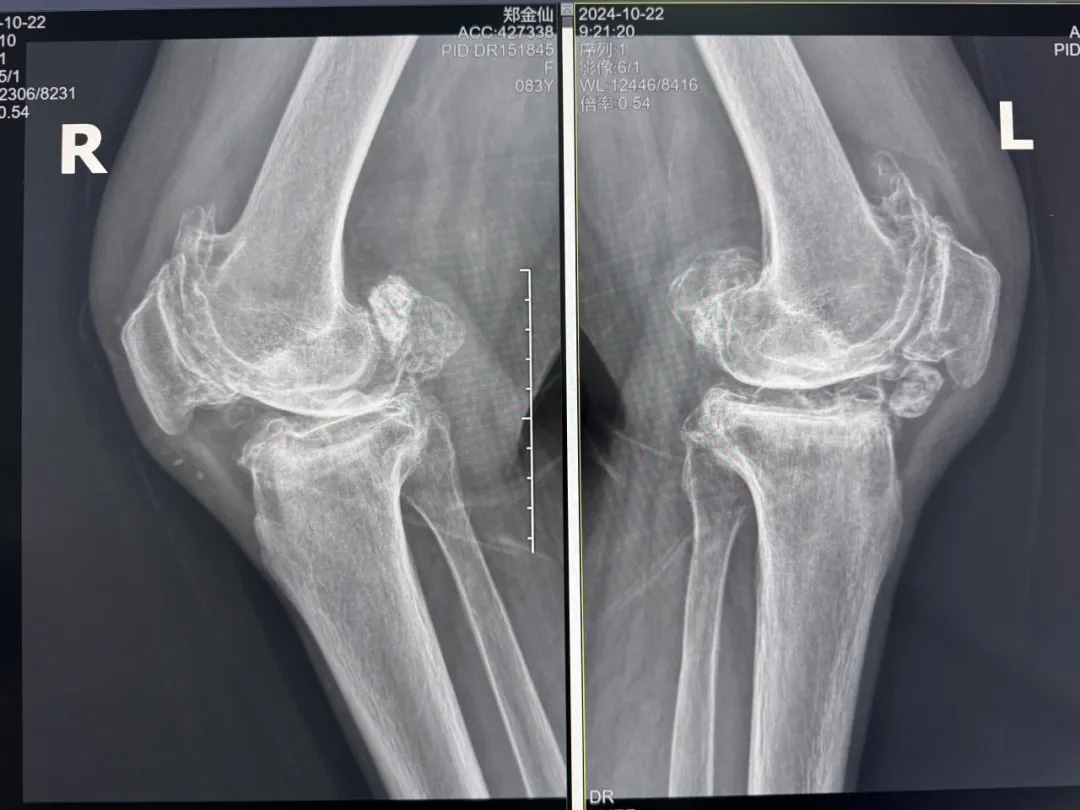

年輕時(shí)愛(ài)到處走走的鄭阿婆,晚年卻被雙膝劇痛困在輪椅上長(zhǎng)達(dá)二十年。經(jīng)羅副院長(zhǎng)診斷,她的膝關(guān)節(jié)軟骨幾乎磨光,關(guān)節(jié)嚴(yán)重畸形,呈"羅圈腿",走幾步便疼痛鉆心,連如廁都需家人抱扶。“我這輩子啊,估計(jì)再也站不起來(lái)了。”是阿婆最常說(shuō)的話。

在家人幾乎放棄希望時(shí),AI三維規(guī)劃技術(shù)為這場(chǎng)"關(guān)節(jié)保衛(wèi)戰(zhàn)"帶來(lái)轉(zhuǎn)機(jī)。